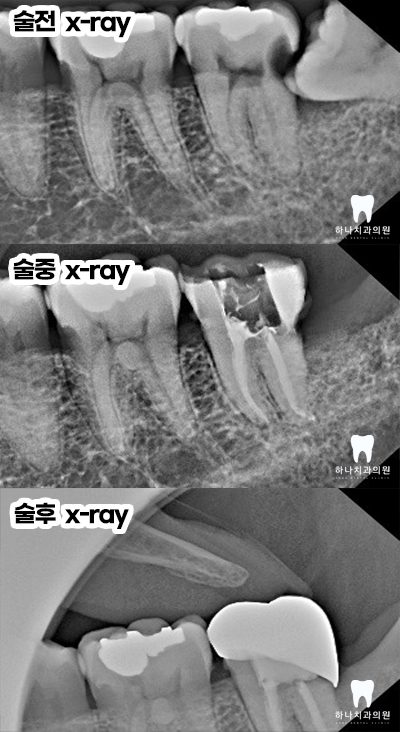

양쪽 아래 수평으로 매복되어 있는

사랑니가 관리되지 않아

바로 앞의 큰 어금니 뒤쪽으로

큰 우식을 공통적으로 가지고 있는

모습을 확인할 수 있었는데요.

오른쪽의 경우, 앞쪽에도 우식이

많이 진행된 상태였습니다.

오른쪽 작은 어금니의 치료 과정입니다.